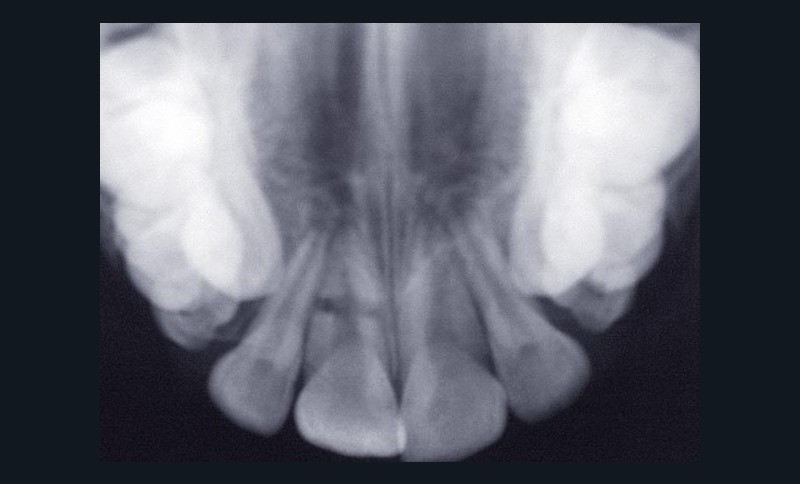

Selon les recommandations de l’InternationalAssociation of Dental Traumatology (IADT) [3], le diagnostic de fracture radiculaire horizontale se fait sur les signes cliniques et sur l’examen radiographique.

À l’examen clinique, le fragment coronaire peut être mobile, déplacé(fig. 1 et 2) et présenter une dyschromie transitoire de la couronne. Dès lors, un certain nombre de tests complémentaires s’impose.

La mobilité. Le degré de mobilité dépend de la situation du trait de fracture [4]. Plus la situation est coronaire, plus la mobilité est importante. Lorsque le trait de fracture est situé au tiers apical, la mobilité peut être physiologique et souvent, dans ce cas, la fracture radiculaire est mise en évidence lors de l’examen radiographique.